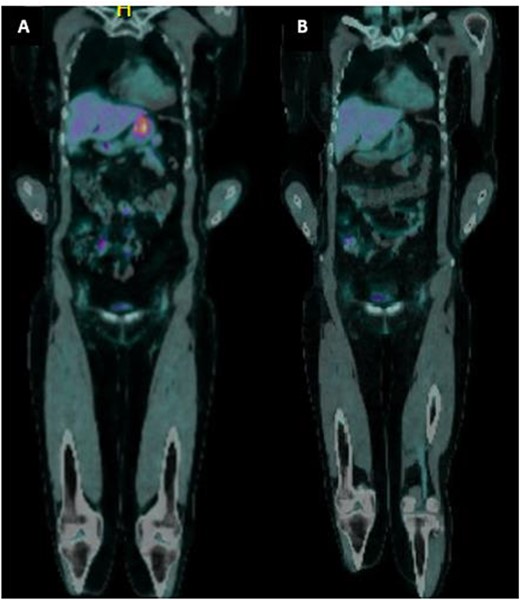

A 65-year-old female was referred to the general surgical outpatient clinic with a 6-month history of epigastric pain and dyspepsia. The patient’s only other medical history was eczema. Physical examination revealed a soft abdomen with no palpable mass. A 10 cm fungating, malignant appearing mass was identified along the gastric lesser curvature on upper gastrointestinal endoscopy (Fig. 1). Histopathology of the biopsied mass demonstrated spindled and small round blue cell tumor with immunohistochemistry staining consistent with Ewing-like sarcoma. Computed tomography (CT) of the abdomen and pelvis showed an enhancing nodular lesion with central calcification and an indeterminate 4 mm lymph node along the lesser curvature of the stomach which raised concerns for gastric malignancy (Fig. 2). Intense fluorodeoxyglucose (FDG) uptake was noted along the lesser curvature of the stomach on staging positron emission tomography (PET) (Fig. 3). There was no evidence of distant metastasis.

(a) PET imaging demonstrated intense FDG uptake along the lesser curvature of the stomach. (b) Interval PET imaging demonstrated reduced FDG uptake at the gastric lesser curvature and reduced gastric wall thickening.

The patient was planned for a 12-week neoadjuvant chemotherapy following discussion with the sarcoma unit and upper gastrointestinal multidisciplinary meeting but her treatment was ceased on the 7th week due to side effects from her chemotherapy regime (Doxorubicin, Vincristine, Cyclophosphamide, Etoposide, Ifosfamide). Interval CT of the abdomen and PET imaging showed reduced FDG uptake at the gastric lesser curvature and reduced gastric wall thickening (Figs 2 and 3).